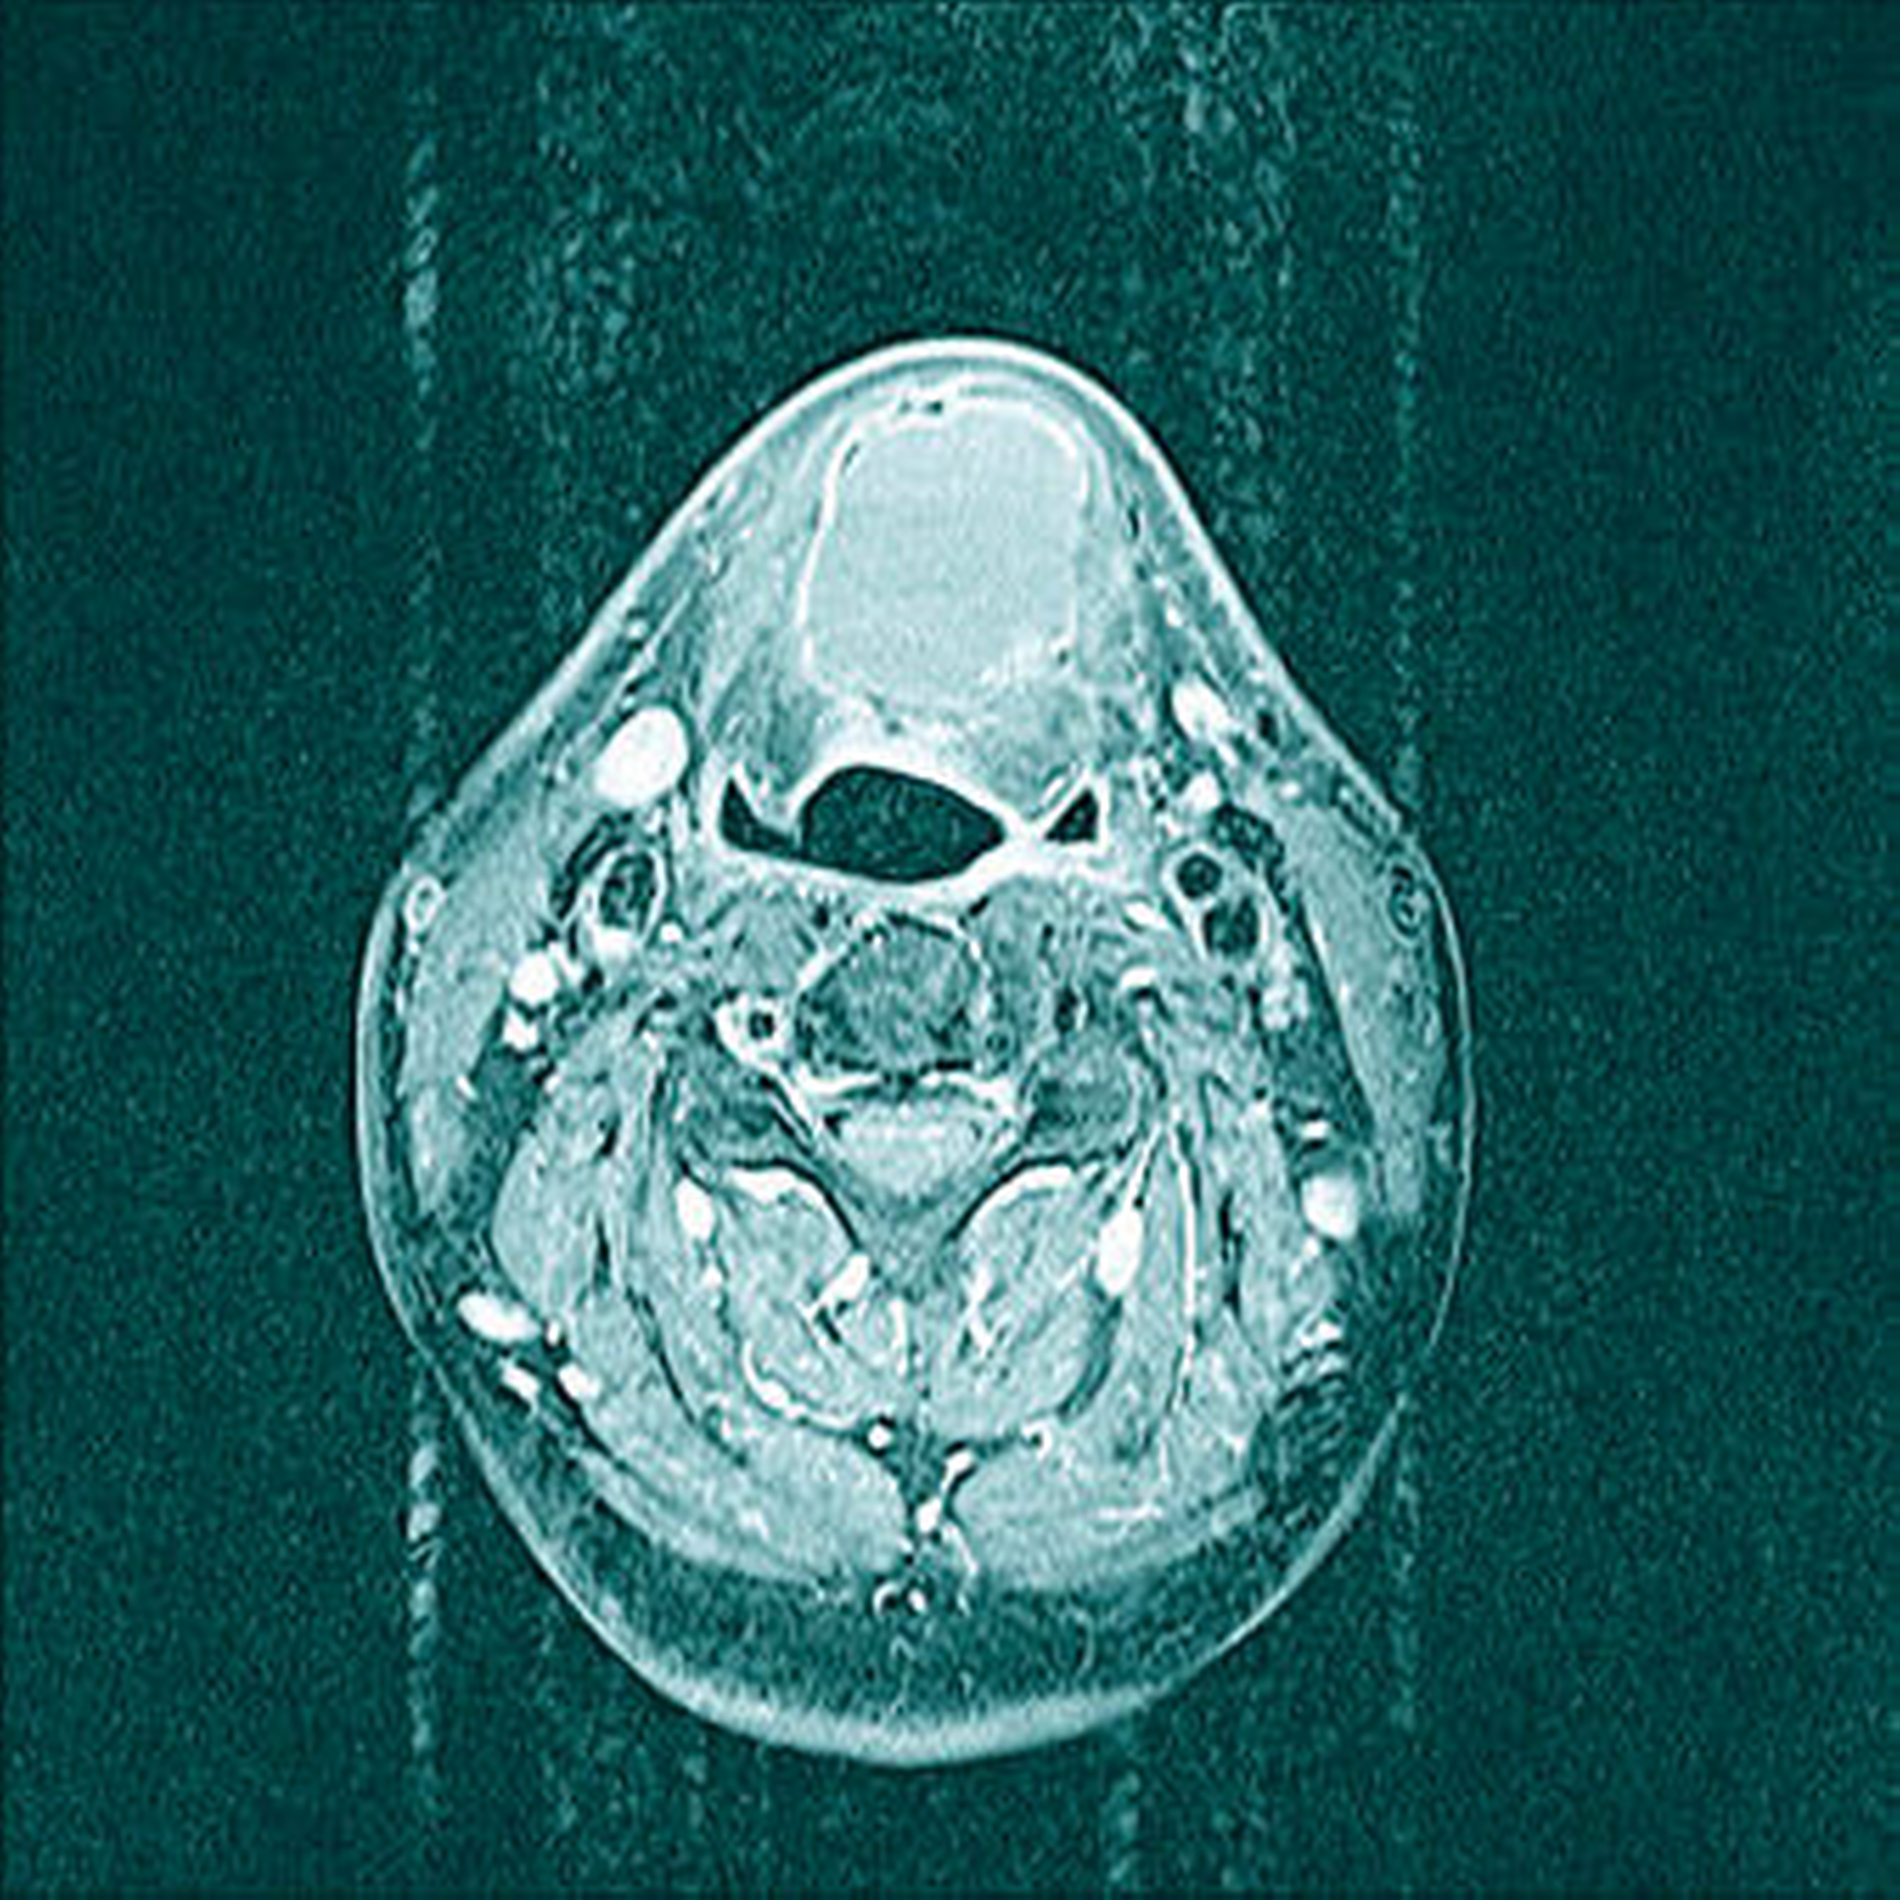

Die unter ambulanten Bedingungen angefertigte schnittbildgebende MRT-Untersuchung des Halses zeigte eine 41×35×27 mm große, gut abgrenzbare und abgekapselte Raumforderung mit homogener Binnenstruktur. Die Dichtewertmessung wies anhand der Verteilung der Hounsfield-Einheiten einen mit flüssigkeitsäquivalentem Gewebe, gefüllten Hohlraum auf (Abbildung 2a). Dieser war mit einer mittigen Einschnürung in der Medianebene des Halses und in der Mitte des Os hyoideum lokalisiert (Abbildung 2b). Dabei werden die Verdrängung des aerodigestiven, benachbarten Raumes sowie die Anhebung des Mundbodens und der Zungengrundmuskulatur deutlich (Abbildung 2c).